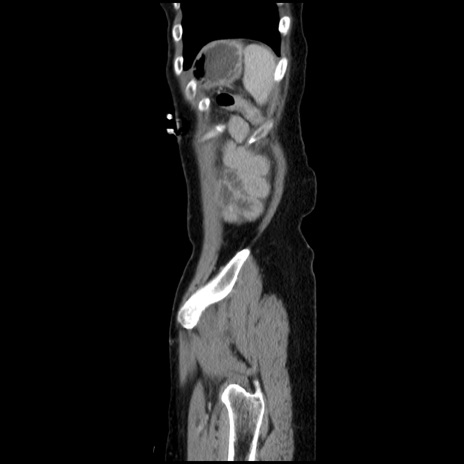

横断像

【症例】40歳代 女性

【主訴】上腹部痛、嘔気・嘔吐

【現病歴】約9時間前頃から急に上腹部痛、嘔気、嘔吐が出現。改善しないため救急要請。

【既往歴】子宮頚癌(広汎子宮全摘術、放射線療法)、腸閉塞

【身体所見】腹部:平坦、軟、腸雑音亢進、上腹部を中心に腹部全体に圧痛あり。

【データ】WBC 8400、CRP 0.03